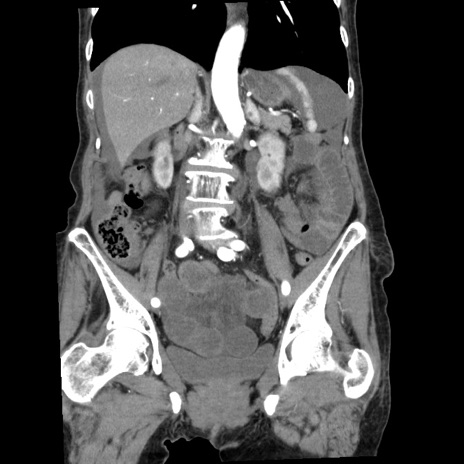

矢状断像

【症例】80歳代女性

【主訴】腹痛

【現病歴】8時間前から腹痛あり来院。

【既往歴】糖尿病、脂質異常症、子宮体癌にて子宮全摘術

【身体所見】意識清明・会話良好だが腹痛で苦悶様、全腹部にわたって反跳痛と圧痛あり

【データ】WBC 13600、CRP 0.14、LDH 224、CK 90